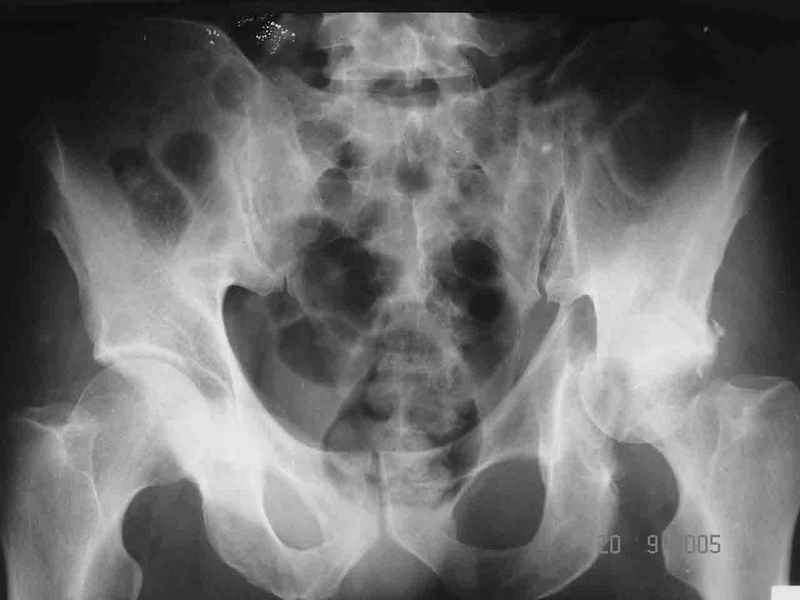

Re: Перелом acetabulum и проксимального отдела бед

Привет! Вот недавно прооперировали похожий на ваш случай - впадина + шейка (правда у нас впадина поперечный+задний край). После травмы прошло 4 недели. мужчине 46 лет. С такой комбинацией все показания к первичному протезированию. Морально и технически мы к этому уже созрели.Но больной не собрал денег на протез. Выполнили остеосинтез впадины и шейки, прекрасно понимая, что головка вскоре рассосется, мы хотя бы надемся что к этому времени таз срастется, как говорится создали все условия для дальнейшего протезирования (может, и протез в последующем подешевле будет, в смысле, без укрепляющего кольца?). Привет Рункову!

Привет Алекей! Сделано неплохо, поздравляю, хотя второй винтик можно было бы и подлиннее в шейку загнать! Пара вопроов: доступ такой же? головка была свободной или висела на капсуле?

Согласен, можно было и подлиннее. Доступ такой же - чрезвертельный, только разрез кожи прямой (а не Y, чего то я разницы не ощущаю). Головка была абсолютно свободной (то есть во время остеосинтеза таза лежала в стакане и не мешалась). Шансов, что она прирастет 0,00001%. Хотели даже выбросить, но привинтили как временный биологический протез (читай свободный трансплантат), чтоб на период срастания таза бедро проксимально не ушло (может ортопеды потом спасибо скажут). Ну а у вас первичное протезирование при переломе впадины тоже пока полько в планах?